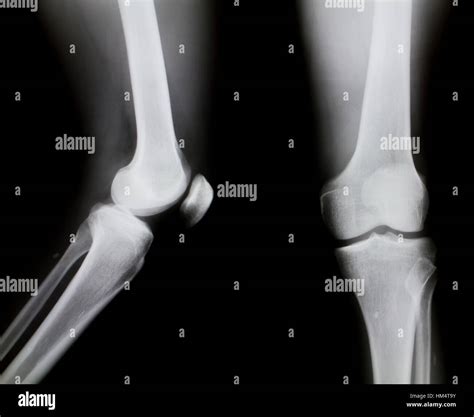

Healthy Knee Xrays

Interpreting Healthy Knee X-rays

Interpreting knee X-rays requires a trained eye. Here are some key features that radiologists look for in Healthy Knee X-rays:

• Bone Structure: The bones of the knee, including the femur, tibia, and patella, should appear smooth and intact without any fractures or deformities.

• Joint Space: The space between the bones should be uniform and not narrowed, which can indicate wear and tear or arthritis.

• Soft Tissue: While X-rays primarily show bone, the soft tissue around the knee should appear normal without any signs of swelling or inflammation.

• Alignment: The knee joint should be properly aligned, with no signs of dislocation or misalignment.

• knee xray side view